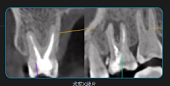

右上后牙酸痛的根管再治疗

慢性根尖牙周炎根管再治疗

慢性根尖牙周炎根管再...